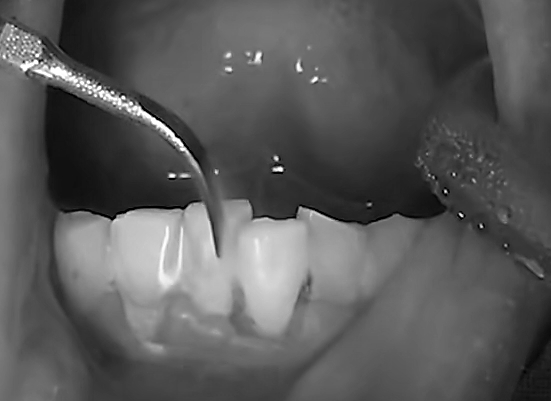

대부분 마취하지 않고 초음파 기구로 치석제거를 하지만

염증이 심하고 치석이 잇몸 깊숙이 파고 들어가 있는 경우에는 초음파 기구와 수기구를 함께 사용해서 치석을 제거합니다.